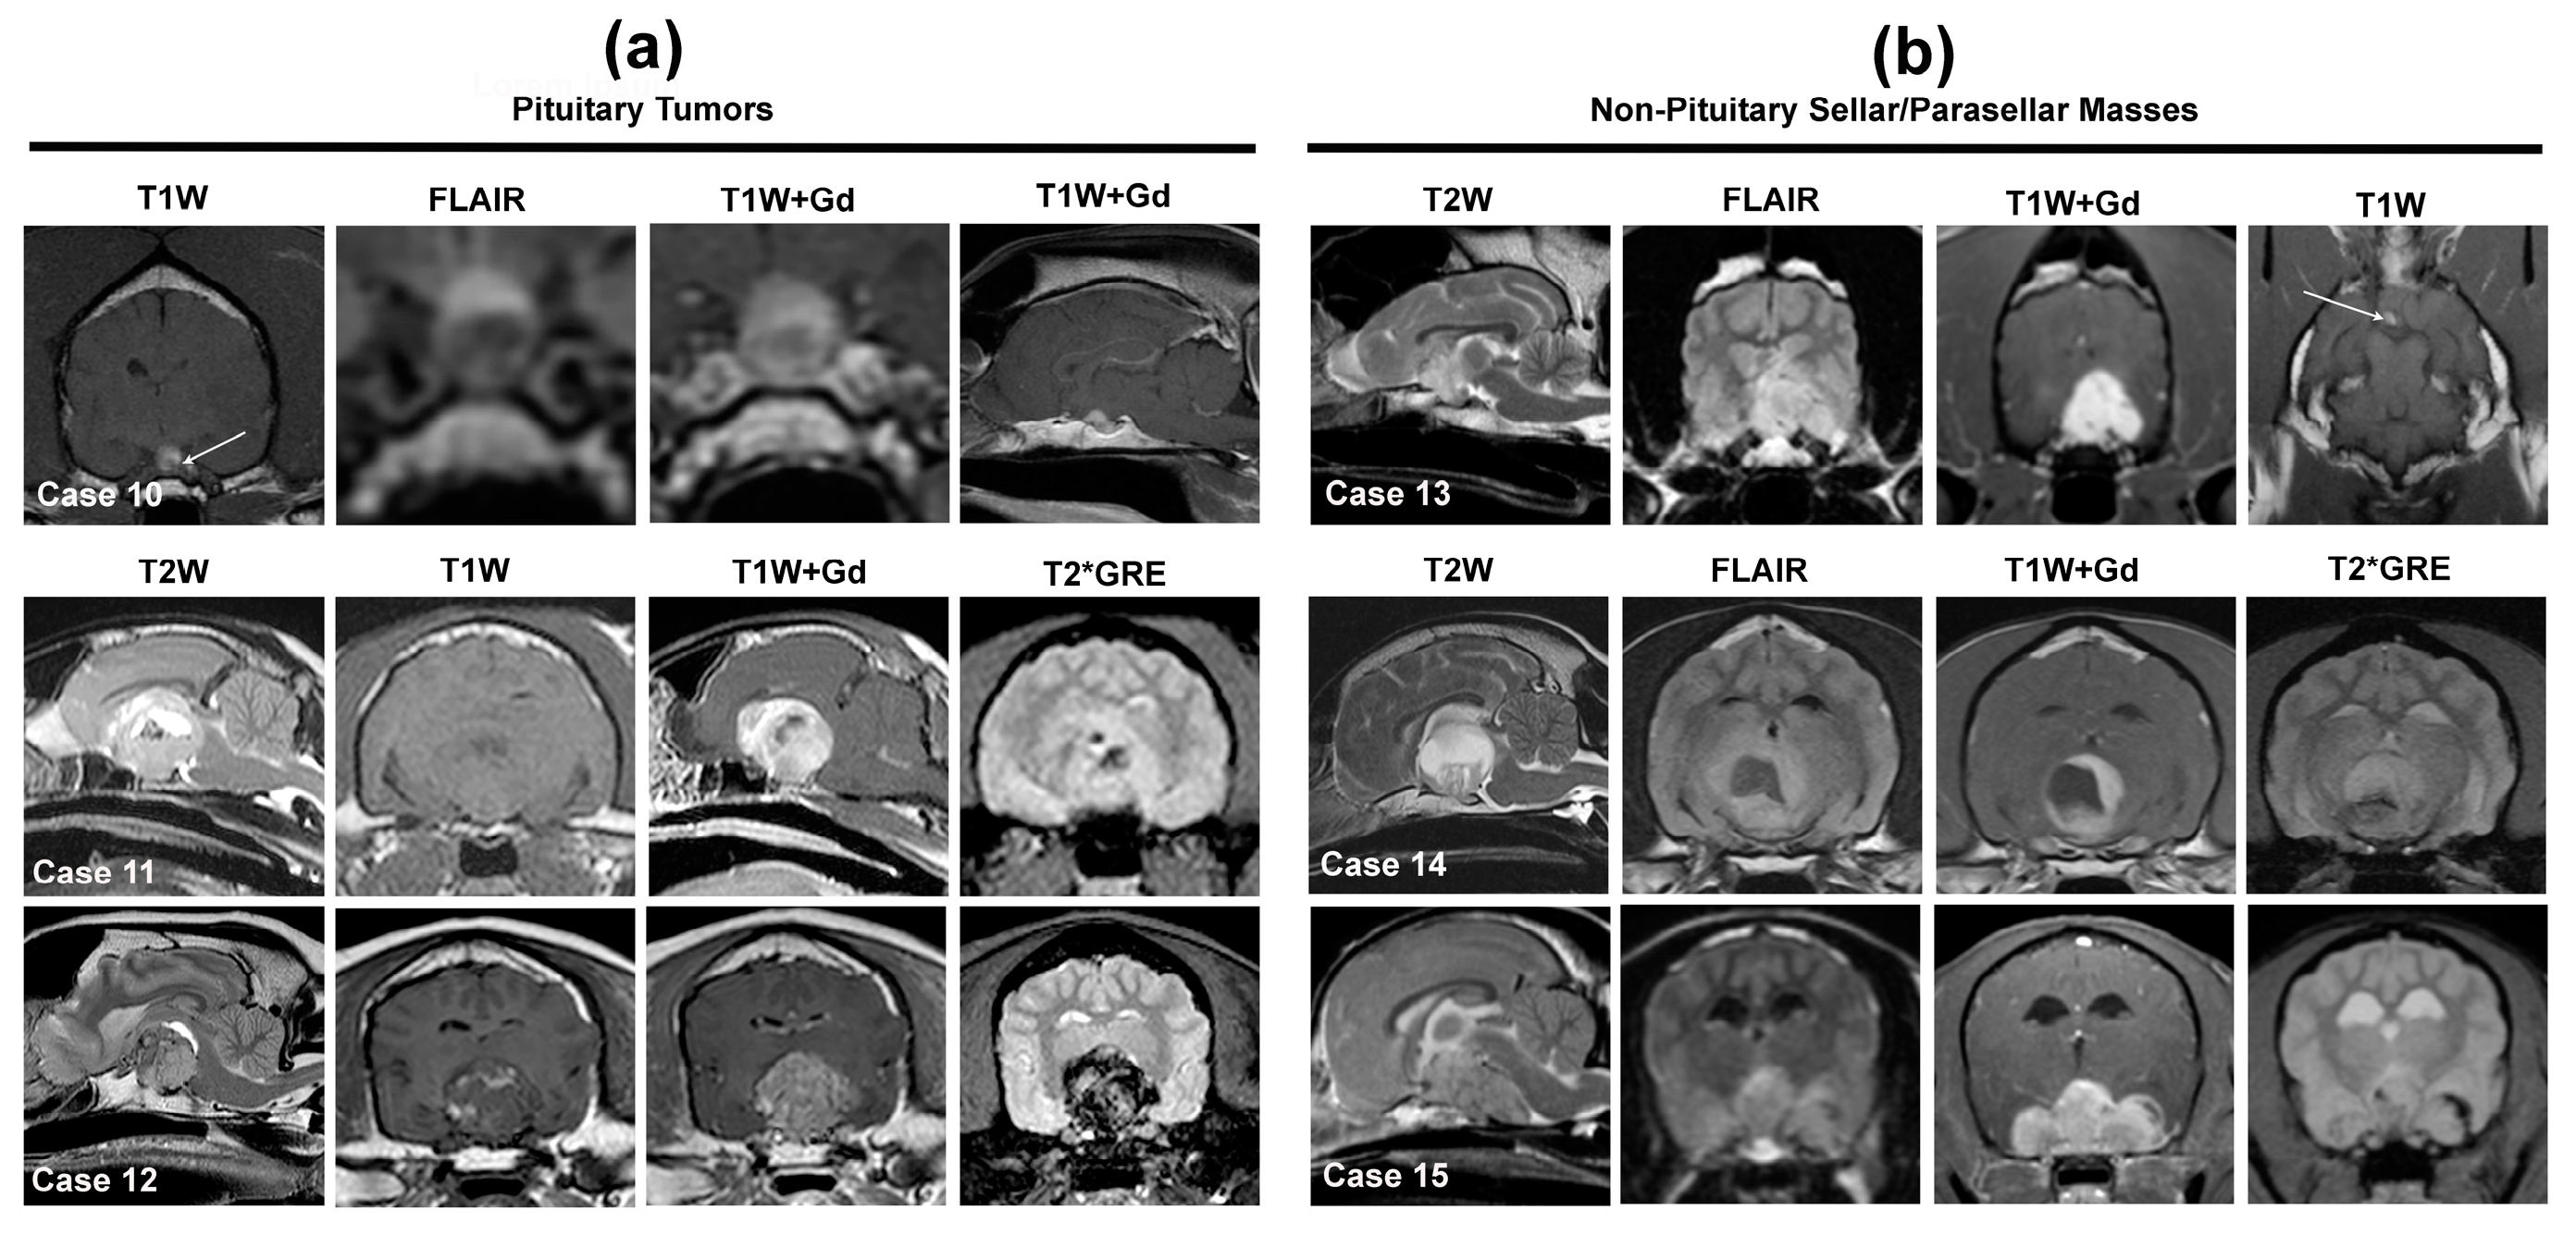

3.2. Solitary Sellar and Parasellar Extra-Axial Mass Lesions

3.2.1. Sellar and Parasellar Mass Lesions of Pituitary Origin

3.2.2. Sellar and Parasellar Mass Lesions of Non-Pituitary Origin